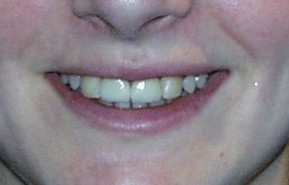

Mundfotos im Vergleich

Vor und nach der Zahnverbreiterung